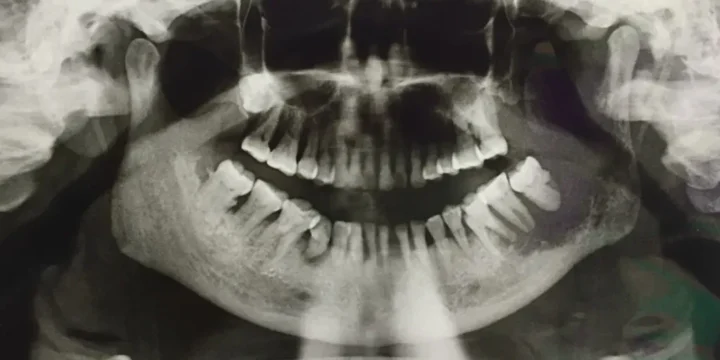

When it comes to insurance, there are differences between corporate and independent dental offices. When insurance is the main point for the patient, it is important to understand the power the insurance company holds over the patient’s health.